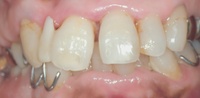

前歯が重なっていたため、歯周病になり、右上の真ん中から二番目の歯が

抜歯になった症例です。

真ん中の歯も傾きがひどく、

このまま削ってブリッジにするには、神経を取らなければならないほどです。

そこで、ほんの少しだけ、矯正治療をしました。

そして、ブリッジが入りました。

初めのころと比べると、とても美しくなりました。